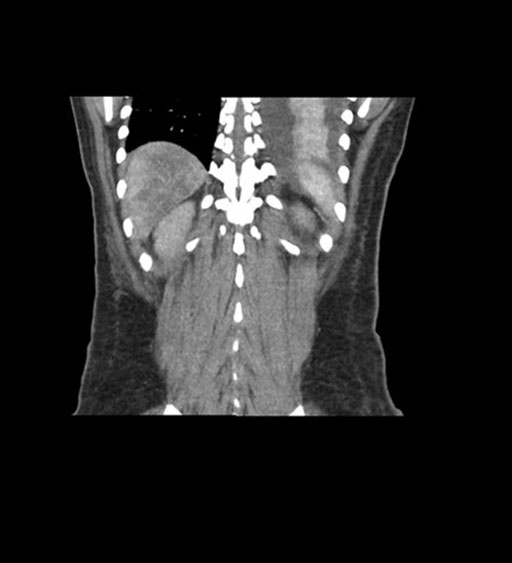

Coronal Venous